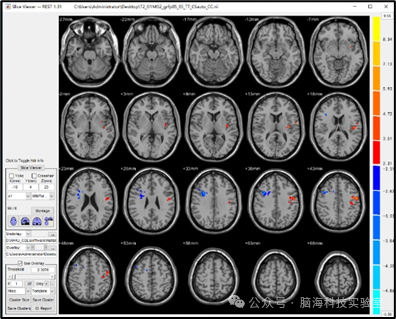

可视化时,通常根据t值的正负与大小设置颜色:

t值为正(升高)→ 暖色

t值为负(降低)→ 冷色

随着t绝对值增大,颜色逐渐加深(或变亮)。

可通过Misc → Set Overlay‘s Color bar调整配色方案,效果相同。

图片

两种不同的颜色条显示可视化,左(jet)右(12).